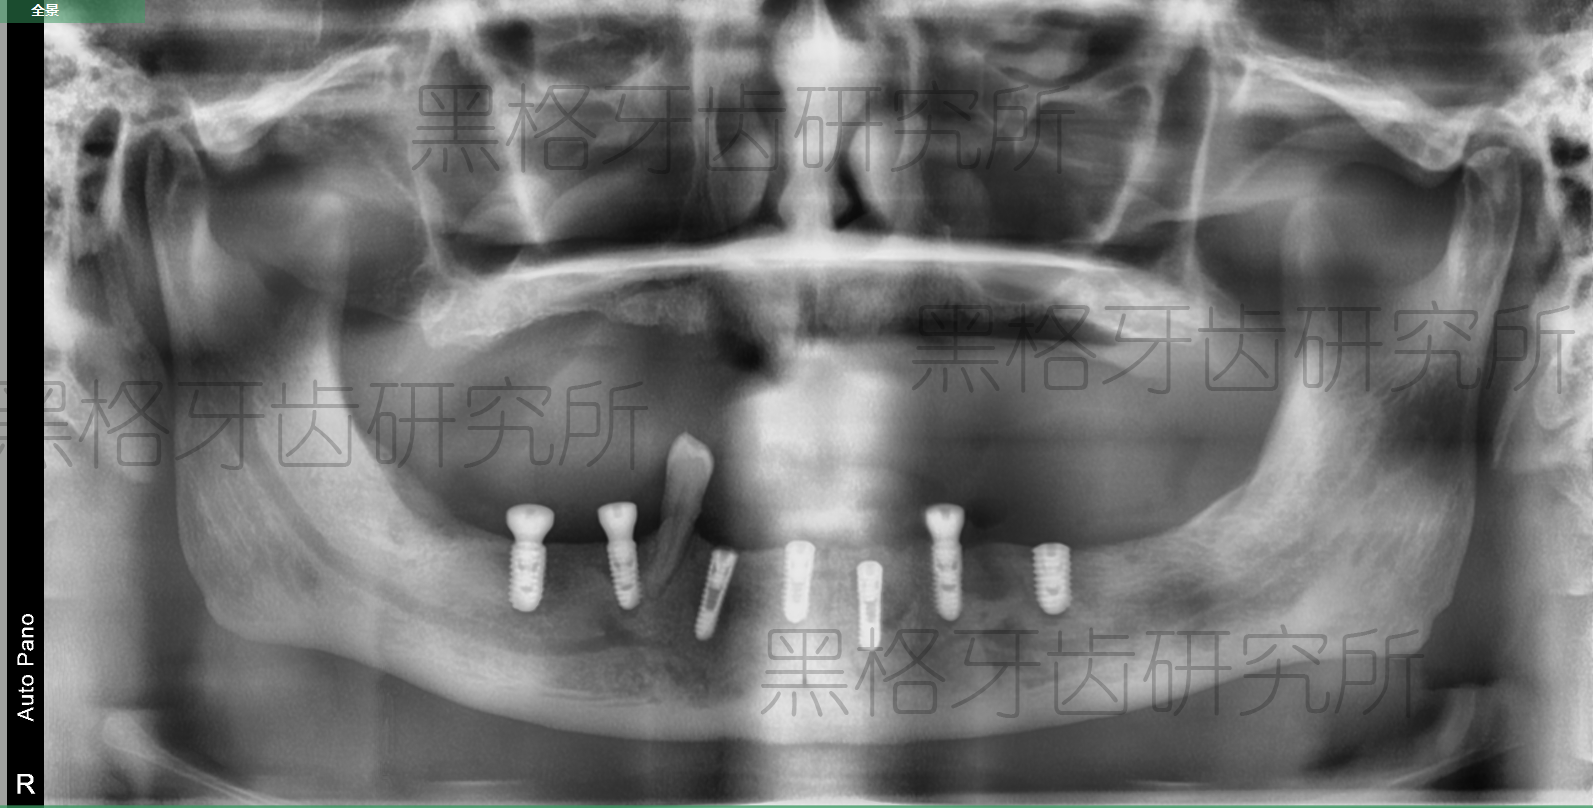

梁阿伯種植后牙片展示

手術(shù)開始后,院方使用了黑格科技提供的種植方案和種植導(dǎo)板,在不到一個(gè)小時(shí)的時(shí)間里,就順利完成了7顆種植體的種植,整個(gè)過程對(duì)牙齦和牙槽骨的傷害極小,麻藥過后梁阿伯也沒有感受到多少疼痛或不適。

因?yàn)榛旧鲜菍儆谌谌笔В葬t(yī)院準(zhǔn)備讓梁阿伯做兩次手術(shù),第一次種植下頜牙列,第二次種植上頜牙列。在方案選擇上,醫(yī)生根據(jù)梁阿伯的牙槽骨情況,終選擇種植7顆種植體,并在電腦上向梁阿伯展示了方案。